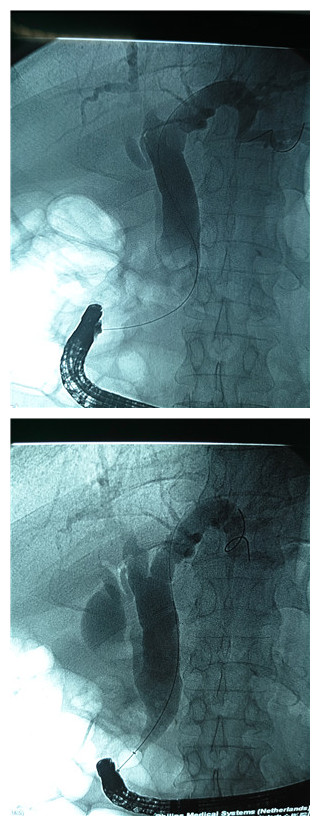

首先曹鹏医生对患者行术前胃镜检查,发现毕II式术后,患者肠管自胃吻合口分输入袢,输出袢,十二指肠乳头位于输入袢。找到十二指肠乳头后发现乳头与我们平时镜下看到的位置完全反转,由于内镜及所有附件均为正常结构下所设计,此例病人无法进行常规内镜下的十二指肠乳头扩管。怎么办?曹鹏医生没有放弃,他将乳头切开刀在体外进行塑形,经过反复尝试后终于插管成功,之后又使用与常规镜下操作完全相反的手法对患者进行胆管造影,可见胆管扩张,胆管内有两枚直径约1.8cm的巨大结石,随后行乳头括约肌切开+胆管末端柱状球囊扩张+机械网篮碎石取石+球囊清理+鼻胆管引流,顺利将患者胆管内的巨大结石取出,免除患者外科开腹手术之苦。

X线下造影成功